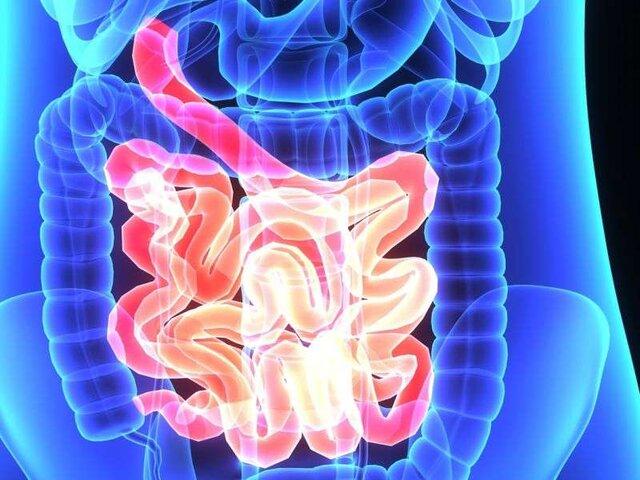

روده یکی از ارگانهای پیچیده بدن است و اهمیت آن برای وضعیت کلی سلامت موضوع بسیاری از تحقیقات جامعه پزشکی است.

به گزارش ایسنا، طی دو دهه گذشته مطالعات متعددی انجام گرفته که حاکی از ارتباط بین سلامت روده و سیستم ایمنی، خلق و خو، سلامت روان، بیماریهای خود ایمنی، اختلالات غدد درون ریز، بیماریهای پوستی و سرطان است.

اصطلاح "میکروبیوم روده" به طور خاص به میکروارگانیسمهای موجود در روده اشاره دارد. یک فرد حدود ۳۰۰ تا ۵۰۰ گونه مختلف باکتری در دستگاه گوارش خود دارد. در حالیکه برخی از میکروارگانیسمها برای سلامتی ضرر دارند، بسیاری از آنها برای بدن بسیار مفید و حتی ضروری هستند.

وجود طیف گسترده ای از باکتریهای مفید در روده میتواند عملکرد سیستم ایمنی بدن را بهبود بخشد، علائم افسردگی را برطرف ساخته، به مقابله با چاقی کمک کند و با هزاران فایده دیگر برای بدن همراه است.